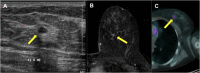

Breast metastases from extramammary cancers are rare and usually related to poor prognosis. The extramammary tumours most frequently exhibiting breast metastases are melanoma, lymphomas, ovarian cancer, lung and neuroendocrine tumours, and sarcomas. Owing to the lack of reliable and specific clinical or radiological signs for the diagnosis of breast metastases, a combination of techniques is needed to differentiate these lesions from primary breast carcinoma or even benign breast lesions. Multiple imaging methods may be used to evaluate these patients, including mammography, ultrasound, MRI, CT and positron emission tomography CT. Clinical and imaging manifestations are varied, depend on the form of dissemination of the disease and may mimic primary benign and malignant breast lesions. Haematologically disseminated metastases often develop as a circumscribed mass, whereas lymphatic dissemination often presents as diffuse breast oedema and skin thickening. Unlike primary carcinomas, breast metastases generally do not have spiculated margins, skin or nipple retraction. Microlobulated or indistinct margins may be present in some cases. Although calcifications are not frequently present in metastatic lesions, they occur more commonly in patients with ovarian cancer. Although rare, secondary malignant neoplasms should be considered in the differential diagnosis of breast lesions, in the appropriate clinical setting. Knowledge of the most common imaging features can help to provide the correct diagnosis and adequate therapeutic planning.